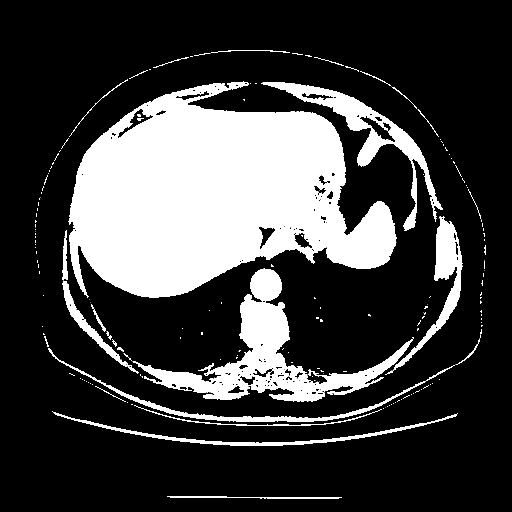

Original VENOUS CT scan

Full window (WL 1023.5, WW 4095 β†’ Low βˆ’1024, High +3071)

Actual HU range: [-1024.0, 3071.0]